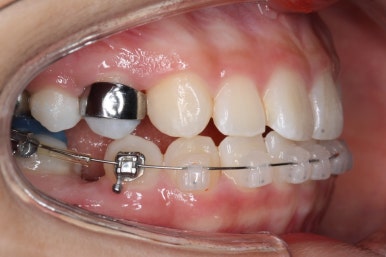

부산치아교정잘하는곳 처음 오셨을 때의 입안 모습입니다.

맨 우측 밑에 사진을 보시면 이가 하나 더 나와야 할 자리에(화살표) 앞뒤로 치아가 쓰러지면서 자리를 거의 없애버렸습니다.

따라서 이가 나올래야 나올 수가 없는 상태였습니다.

왼쪽 맨 위 사진을 보시면 아래 치열의 중앙이 한 쪽으로 쏠린 것을 알 수 있는데요. 역시 치아가 나올 자리가 없어지면서 치열이 쏠러버렸다는 것을 알 수 있습니다.